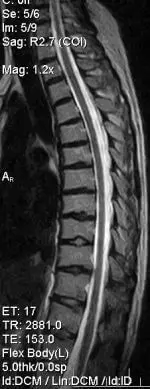

При тривалих і стійких больових проявах з боку хребта, крім МРТ шиї, іноді необхідно робити МРТ-обстеження грудного відділу.

Це необхідно для диференціальної діагностики. Наприклад, ураження грудного відділу хребта метастазом також може викликати біль у шиї: